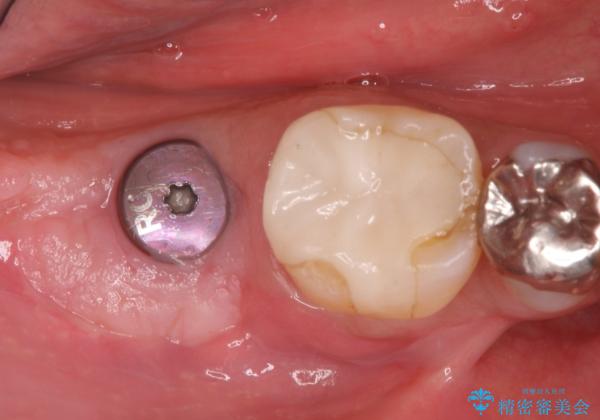

インプラント埋入時に骨が足りない場合にはインプラント埋入前に骨増生を行います。また、インプラント周囲の角化歯肉が不足した場合は角化歯肉の移植も行うことがあります。

どちらの治療もインプラントの長期予後を高めるために必要な治療です。